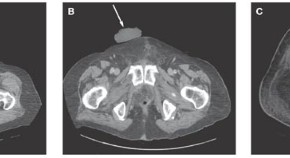

• Small-cell carcinomas of the prostate or high-grade prostate cancer with neuroendocrine differentiation are often lethal phenotypes with no direct pathognomonic symptoms. This article presents the case of a 52-year-old man diagnosed with high-grade prostate cancer and small-cell/neuroendocrine features who was managed with transurethral resection, androgen blockade, total pelvic exenteration, nephrostomy placement, and chemotherapy. The author highlights the treatment and management course in such patients and the need for early diagnosis of this aggressive type of tumor.